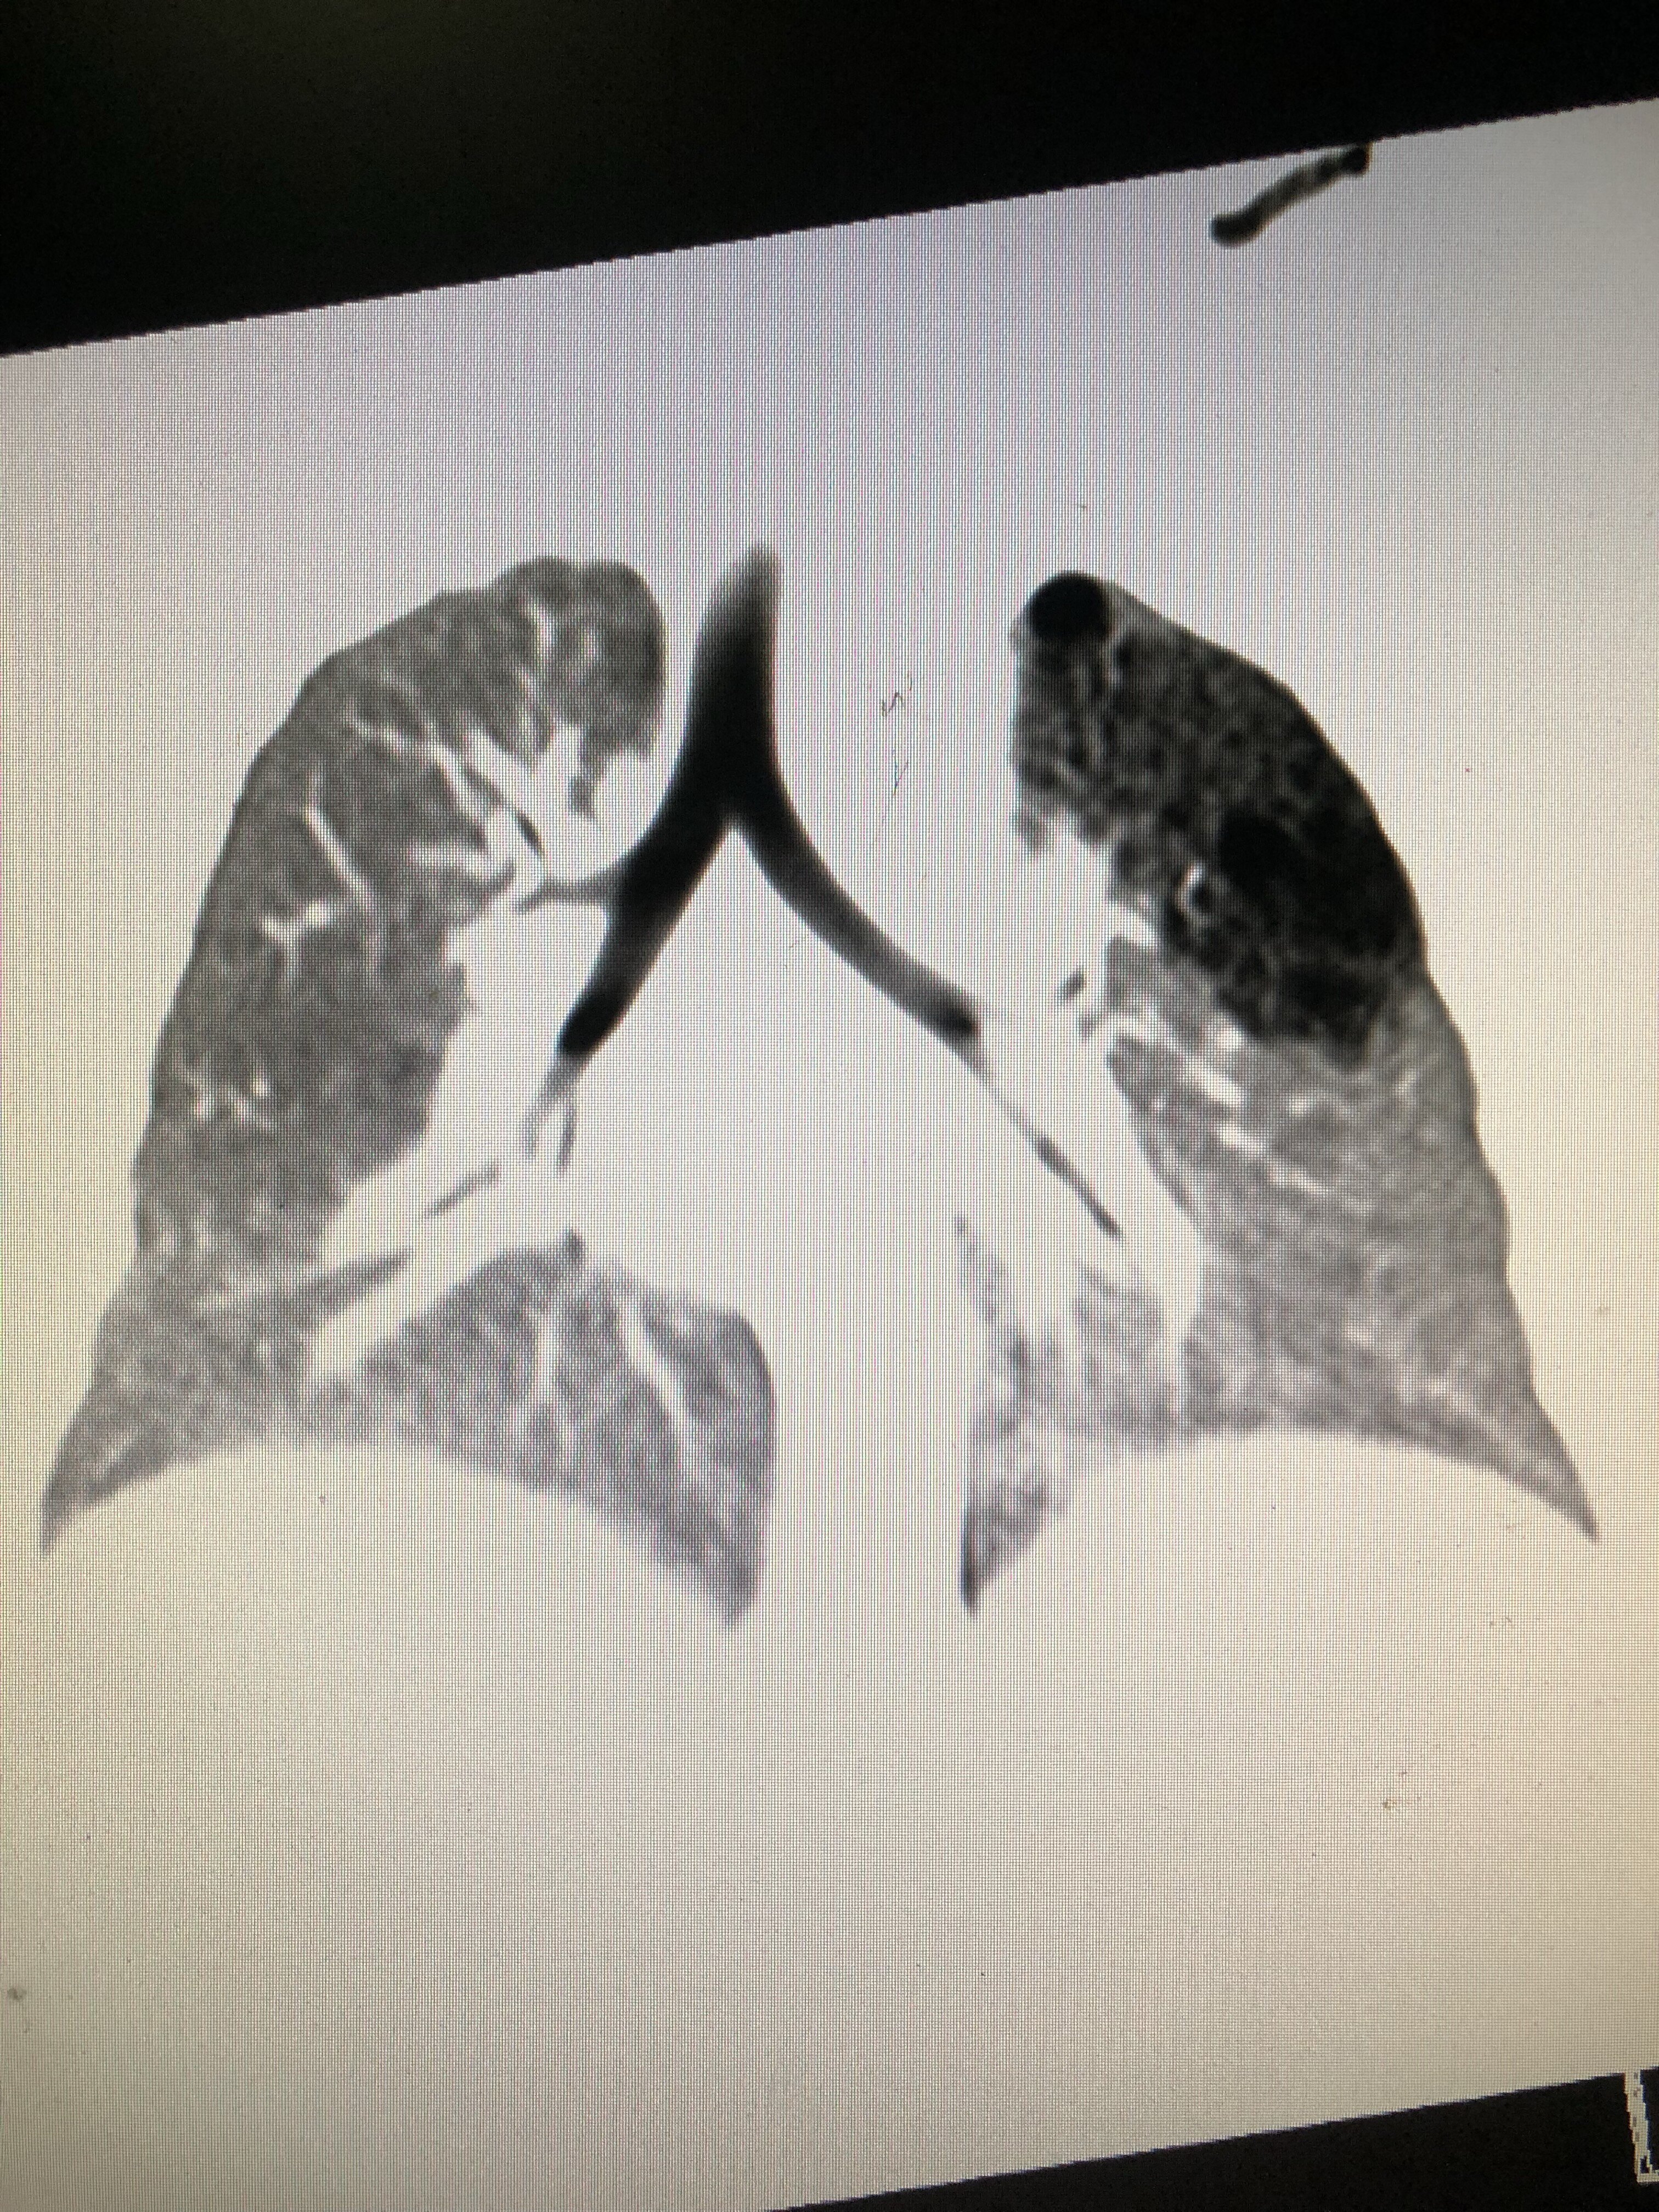

“阳康之后发觉的肺囊肿,绝大多数都是良性,是病毒传染后在肝脏留下的病变影,最典型的就是磨玻璃病变影。这个时侯发觉的脑部阴影,肾脏的病变,千万不要急着下定论,由于特殊灾情大流行其间,大多都是传染造成,一定要等候观察,再决定下一步诊治。”

肺囊肿,是指肺部半径大于或等于3公分的类方形或不规则形病变。为何不少人“阳康”后,查CT查出了肺囊肿呢?

二是当初没有,传染后来发觉的。任何传染都有或许产生肺囊肿,随着新冠病毒传染的治愈,有的肺囊肿或许会消失,有的肺囊肿或许会常年存在。

上海老年诊所喘气一科主治医师蒋贝兰2022年4月在该院人民晚报健康号刊文介绍,产生肺囊肿的症状非常多,包括普通肝炎、肺疟疾、真菌传染、尘肺、不典型病变、淋巴结、炎性假瘤、陈旧肺腺癌、痰栓、硬化性肺细胞瘤、肺错构瘤、肺癌、转移瘤等等,所以并不是所有的病变就是癌,无意中发觉的病变,非常是年青病人,90%以上都不是癌症。

乔贵宾解释,这并不是由于活检比CT看得更清楚,恰恰是由于膝盖CT看得太清楚了,像这些病毒传染导致的一点点的磨玻璃影,对人体并没有外伤,过一段时间或则1个月左右才会完全消失。病人假如这时拍了手臂CT照出有病变,心理压力都会特别大。